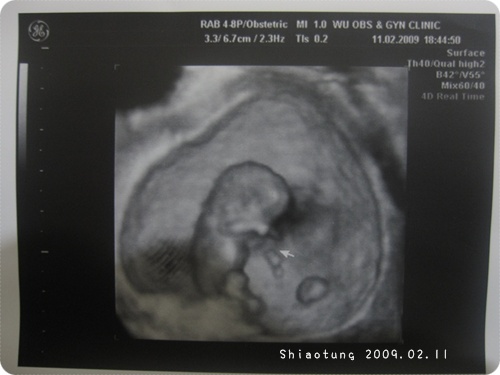

懷孕週數:9

胎兒大小(頭至屁股):約3.01cm →醫生都不會量腿,因為腿哪裡會伸直?

9週熊熊看到就是人型了也!

手腳已經很明顯,

超音波影片裡還不停的揮動...